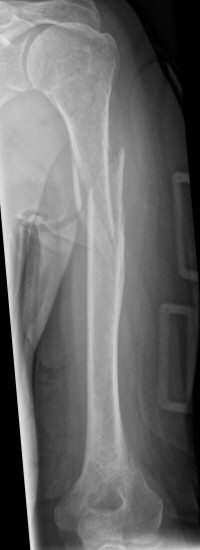

Exempel på humerusfraktur som behandlats icke-kirurgiskt, röntgenbilder efter 19, 40 resp. 71 dagar